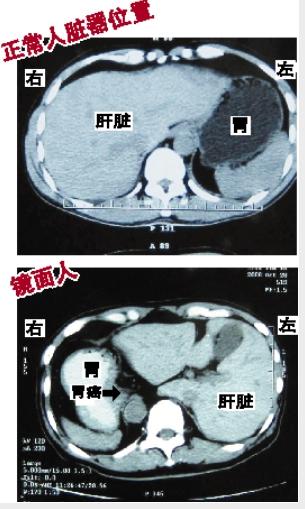

拍CT才知是“镜面人”

王宁家住广州某高校,今年76岁。10月底,他因连续便黑血到医院检查,做胃镜后发现患上胃癌。术前身体检查时,医生拍片发现,患者的心、胃、肝、脾、肠等内脏全部长反了位置。本应长在身体左边的心脏和胃,他却长在右边;而本该长在右边的肝脏、阑尾,他却长在左边;胆囊、胰腺、肠子等脏器,也全部长反了位置。“就像正常人在镜子中的影像一样,王宁是位‘镜面人’。”

正常人

镜面人

心脏、胃长在身体左边

肝脏、阑尾长在右边

心脏、胃长在身体右边

肝脏、阑尾长在左边

胆囊、胰腺、肠子等脏器位置也全部长反了